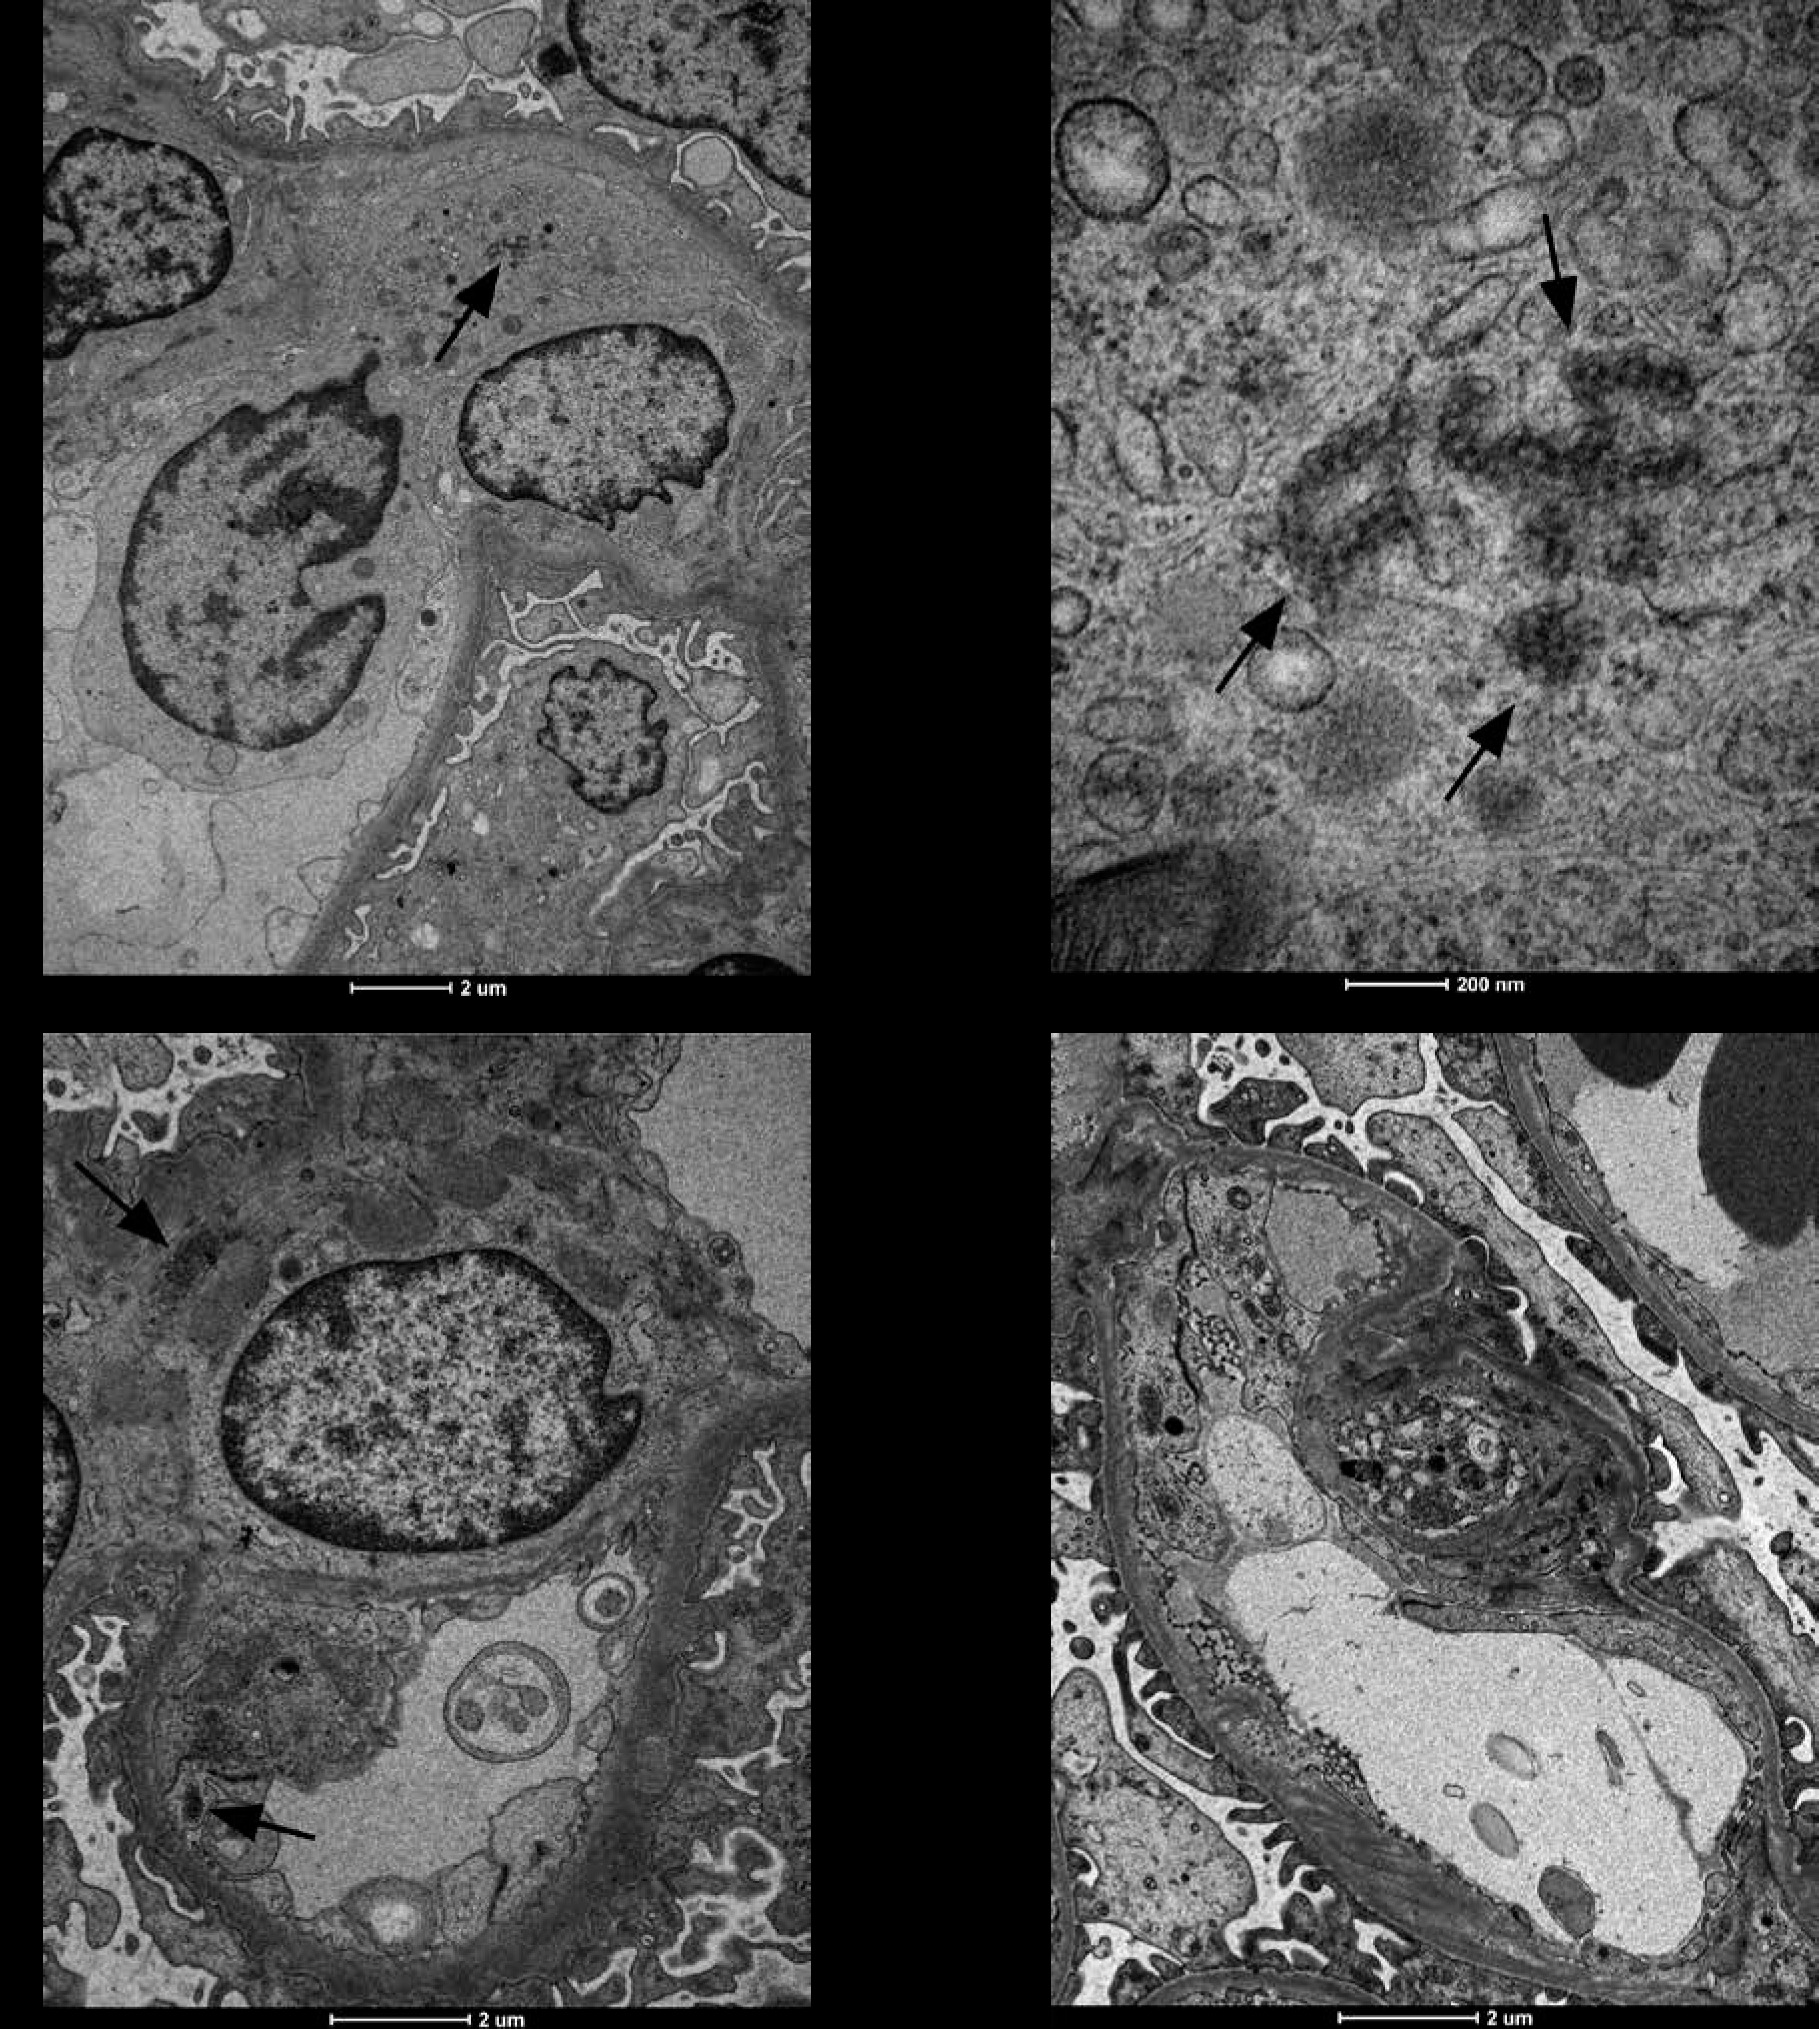

The evaluation of the biopsy samples in a light microscope revealed class III LN in five cases (50%), class II in three cases (30%), and class IV and class V in two individual cases (Table 1). Ultrastructural analysis of the biopsy material showed the presence of TRIs in seven patients (Table 3). These structures were most often found in endothelial cells of both the vascular bundle and the peritubular capillaries. They were occasionally observed in monocytes within capillaries and mesangial fields (Fig. 1). TRIs occurred within the irregularly widened cisterns of the endoplasmic reticulum. Some of them presented signs of pronounced swelling, which led to disruption of the surrounding membranes. In some inclusions, the tubular structures came into close contact with the membranes of the endoplasmic reticulum (Fig. 2). Both the size of the inclusions and the frequency of their occurrence varied among specimens (Fig. 3). The size of the TRIs varied in the range 300-1600 nm. Numerous TRIs (several inclusions in one glomerulus) were found in the biopsy of a patient with class V LN. All patients were tested for the most common viral infections connected with presence of TRIs (HIV, HBV, HCV, EBV, CMV) and all those disorders were excluded by performing simple blood tests. Only in one patient, after three years of treatment, was the re-biopsy performed. TRIs were still present in the specimen, but they were much less abundant (Fig. 4). In three cases with the highest presence of TRIs, the disease began before puberty (at 8-10 years of age), and in all these cases hematological disorders such as leukopenia, anemia, and thrombocytopenia preceded the LN diagnosis. Inclusions in a typical location, near subendothelial deposits, were observed in only one patient (Fig. 5). Biopsies of three patients with disease onset in adolescence (around 14 years of age) revealed no TRIs in the sampled material. In these patients, arthritis and nephrotic proteinuria dominated the clinical picture.

Fig. 2

A, B) Evident tubuloreticular inclusions (TRIs) visible within the degranulated rough endoplasmic reticulum in renal biopsy samples collected from patients with juvenile systemic lupus erythematosus (jSLE). Full arrowheads indicate loss of the reticular membrane continuity. Open arrowheads indicate adherence of individual tubules to the membranes of the reticulum

Fig. 3

Fragment of a capillary with a highly swollen endothelial appendix containing three tubuloreticular inclusions (TRIs) (arrows) in renal biopsy samples collected from patients with juvenile systemic lupus erythematosus (jSLE)

Fig. 4

The figure shows two biopsies of Patient 6. The first biopsy was performed in 2012: A) TRI structures (arrows) are present in a monocyte, B) endothelial cells and within mesangial area; A1) Enlargement of the photo (A) revealing details of the ultrastructure of TRI structures. The second biopsy (C) performed 3 years after initiation of treatment revealed absence of TRIs